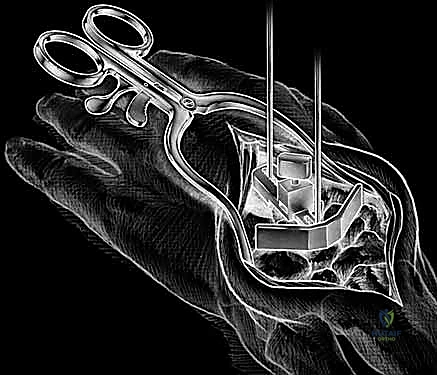

A longitudinal dorsal incision, positioned slightly radial to the midline, is made extending from approximately 4 cm proximal to the radiocarpal joint down to the midpoint of the third metacarpal shaft. Sharp dissection is carried down through the subcutaneous tissues to the level of the extensor retinaculum, taking meticulous care to identify and protect the sensory branches of the superficial radial nerve and the dorsal sensory branch of the ulnar nerve. The third dorsal compartment is opened, and the extensor pollicis longus (EPL) tendon is exposed, mobilized, and retracted radially. The retinaculum is then elevated as a continuous flap. The radial wrist extensors (ECRL and ECRB) are exposed and mobilized radially, while the first compartment tendons are mobilized from the distal radius and protected. The tendons of the fourth and fifth compartments are mobilized ulnarly, ideally without opening their respective synovial compartments to prevent postoperative adhesions.

With the extensor tendons mobilized and safely retracted, a longitudinally based capsulotomy is performed. The capsule is reflected as radially and ulnarly based full-thickness flaps, exposing the distal radius and the entire carpus down to the base of the third metacarpal. Preparation of the distal radius involves scoring a reference line to ensure the DRUJ is preserved. The radial canal is sequentially broached to accept the modular radial stem. The modular radial stem component is designed to fill the distal radius canal to prevent loosening and provide rotational stability. While approved for implantation with bone cement (PMMA), most modern wrists are implanted with press-fit, cementless fixation to encourage osteointegration. Cement is generally reserved for cases of significantly compromised bone stock, severe osteopenia, or revision scenarios.

Following capitate reaming, the chosen carpal plate and stem are assembled and inserted into the capitate and seated onto the resected carpal surface. The carpal plate is anchored to the carpus with a radial screw that optimally does not penetrate the second metacarpal, and a second screw placed ulnarly into the hamate. This construct ensures stable distal fixation while avoiding the deleterious lever arm of a long metacarpal stem. Trial reductions are performed to assess stability, range of motion, and impingement. Once kinematics are confirmed, the definitive ultra-high-molecular-weight polyethylene (UHMWPE) body—which is direct compression molded onto a cobalt chrome alloy radial body—is impacted. The capsule and extensor retinaculum are meticulously repaired to prevent extensor tendon bowstringing and provide a robust soft tissue envelope over the implant.